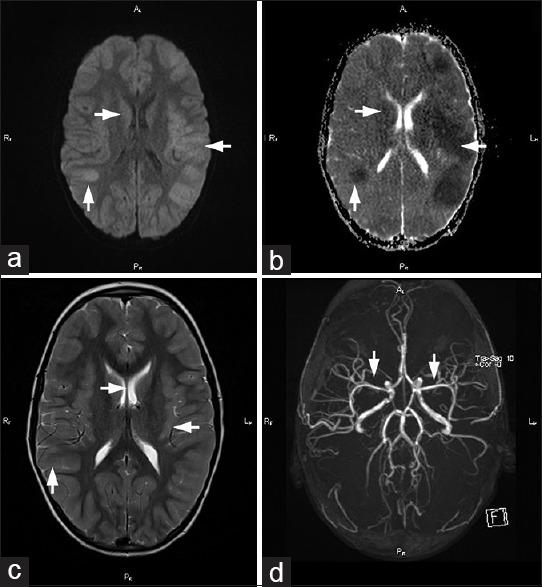

We report a case of a 7-year-old boy with Kawasaki disease (KD) complicated with cerebral vasculitis and encephalitis. The patient was admitted with signs of encephalopathy, seizures, and coma. The diagnosis of KD was made on the 2 day of hospitalization based on the clinical features (fever >5 days, maculopapular rash, nonpurulent conjunctivitis, fissured lips, and cervical adenopathy). Brain magnetic resonance imaging findings suggested cerebral vasculitis. Treatment with intravenous immunoglobulin was followed by mild improvement. After a single dose of immunoglobulin, pulse methylprednisolone therapy was started resulting in gradual improvement of consciousness and eventual complete motor and cognitive function recovery with regression of brain magnetic resonance lesions. KD can present with marked neurological symptomatology. Therefore, it should be considered in the differential diagnosis of encephalitis and encephalopathy etiologies in children.

我们报告一例7岁患川崎病(KD)并发脑血管炎和脑炎的男孩。该患者因脑病、癫痫发作和昏迷症状入院。根据临床特征(发热>5天、斑丘疹、非脓性结膜炎、唇裂和颈部淋巴结病),在住院第2天确诊为KD。脑磁共振成像结果提示脑血管炎。静脉注射免疫球蛋白治疗后稍有改善。单剂量免疫球蛋白治疗后,开始脉冲甲基强的松龙治疗,意识逐渐改善,最终运动和认知功能完全恢复,脑磁共振病变消退。KD可出现明显的神经症状。因此,在儿童脑炎和脑病病因的鉴别诊断中应考虑该病。